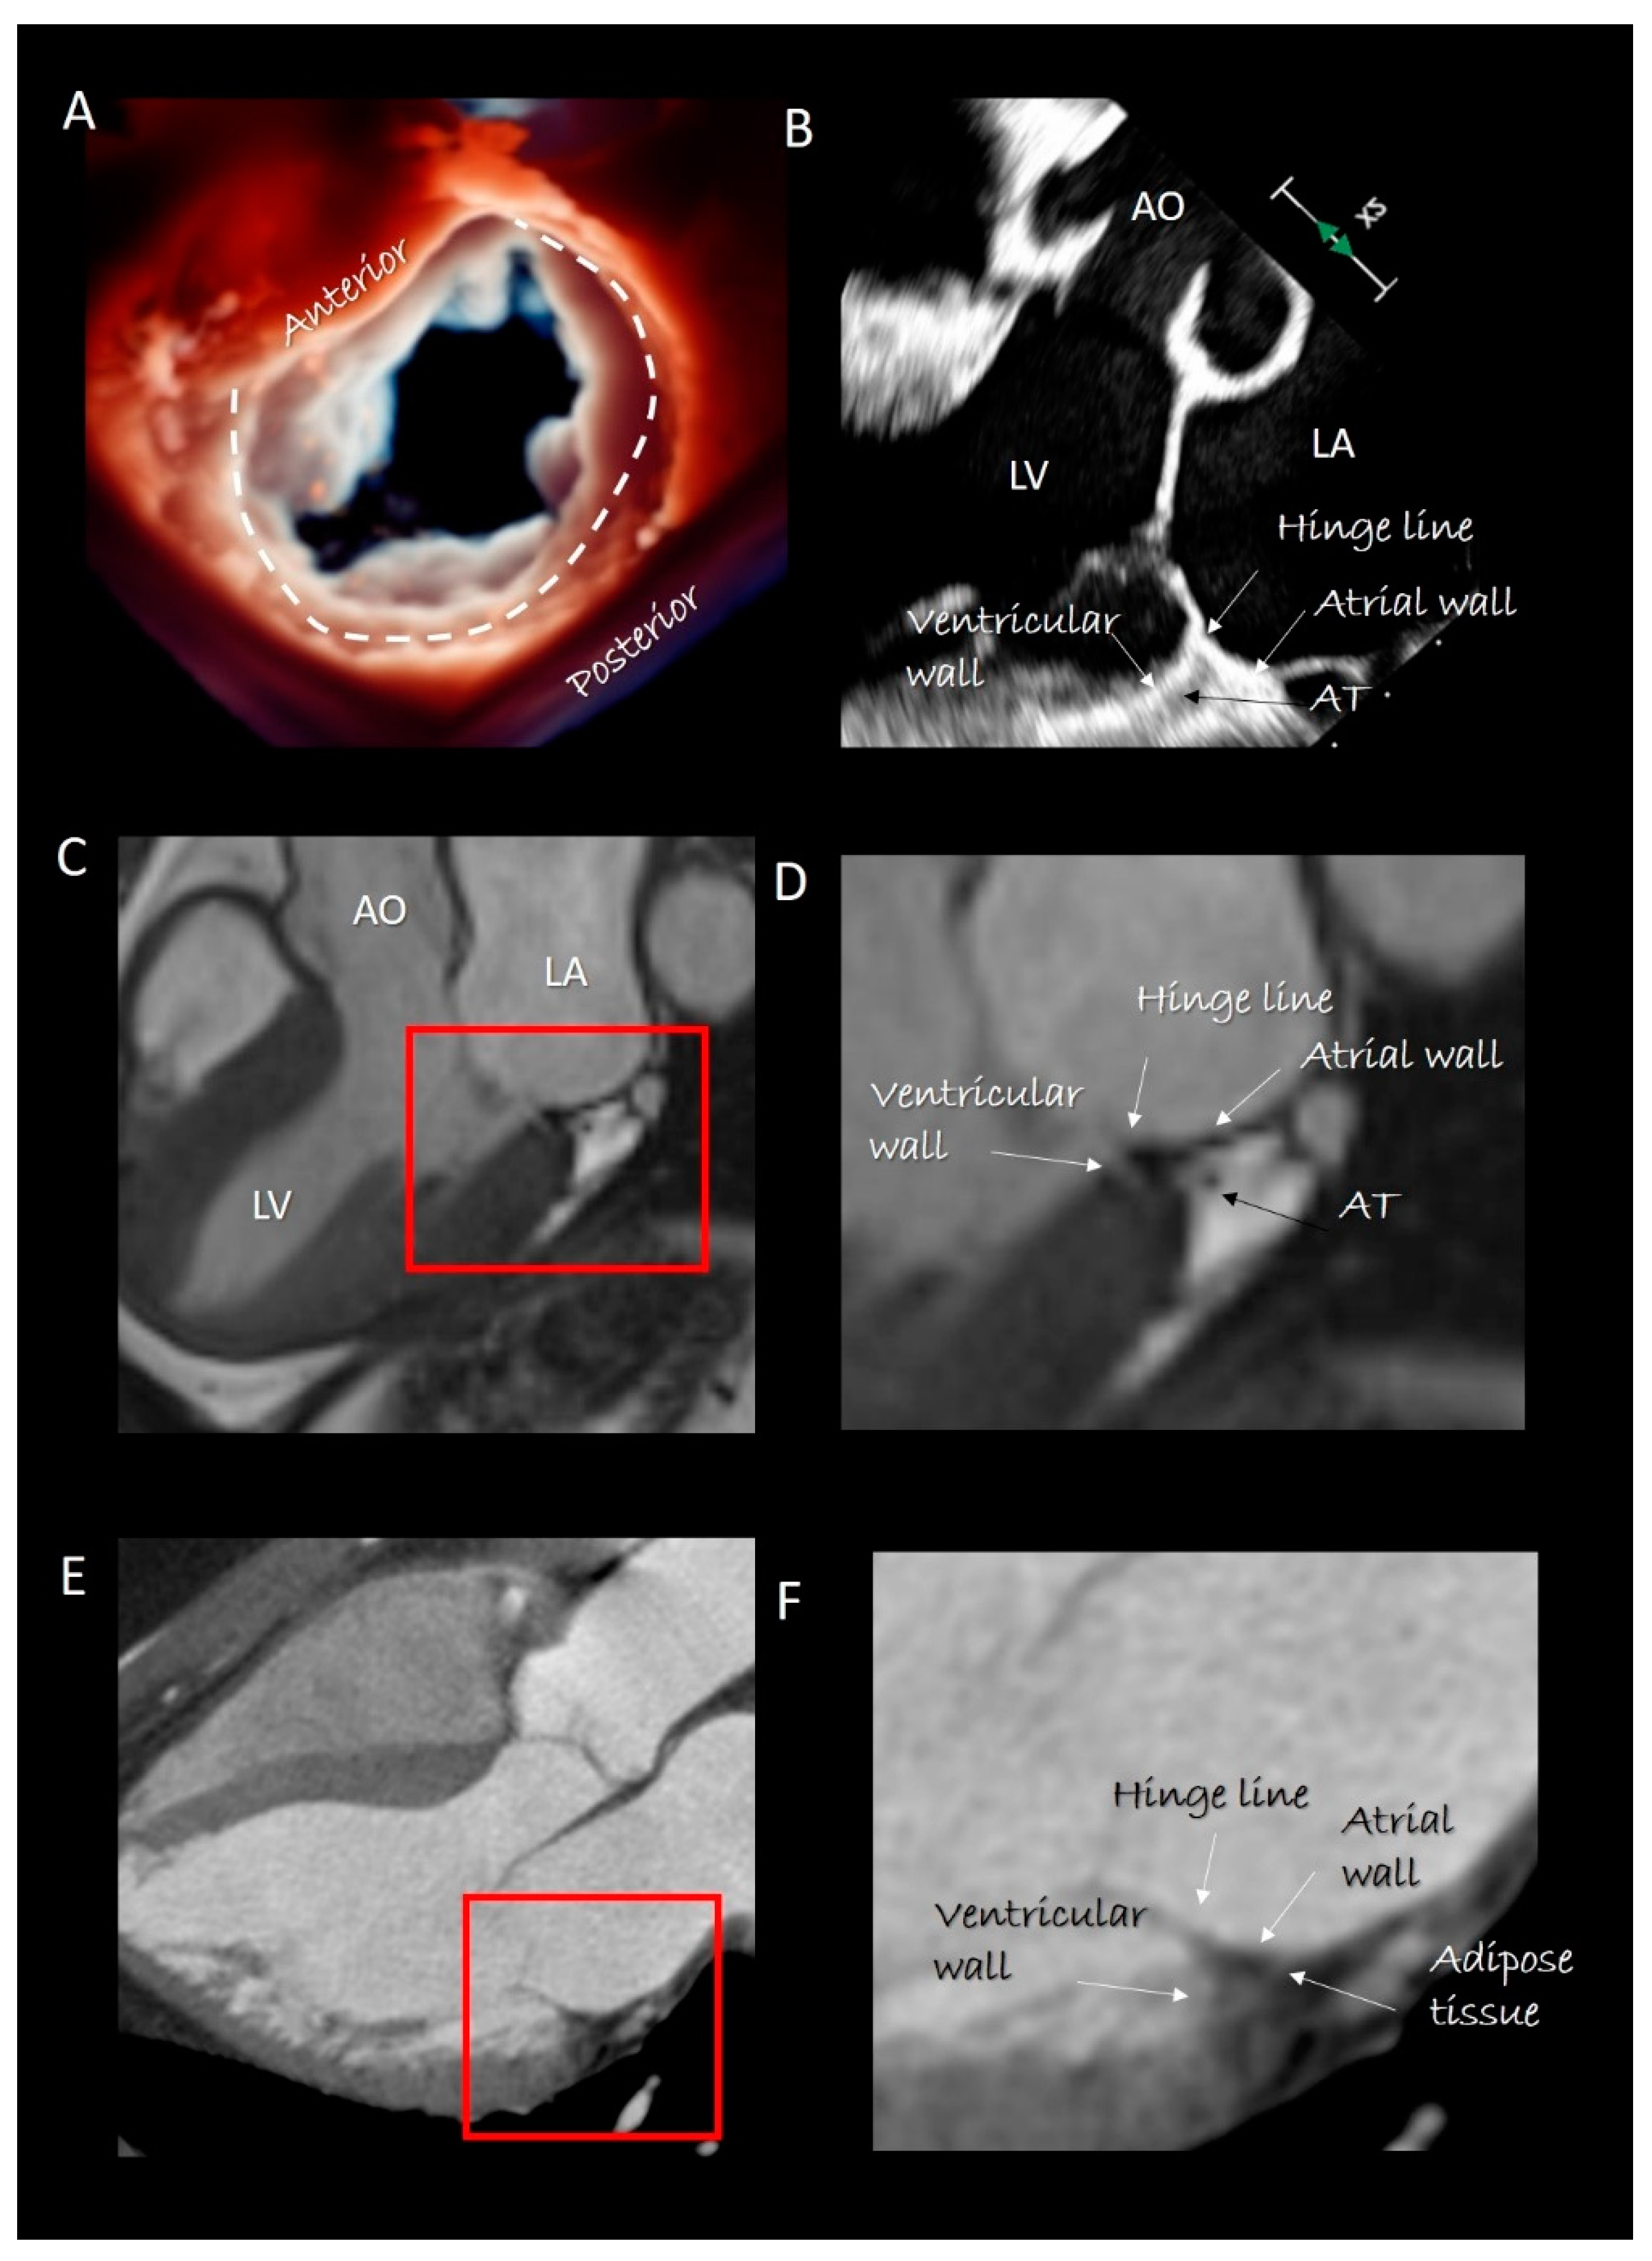

Figure 2.

(A) 3D transesophageal echocardiography (TEE) still frame image of mitral valve forms an overhead perspective with a specific rendering algorithm that permits a movable source of light. With a source of light behind the valve, the two components of mitral annulus are well visible (the curved dotted line marks the posterior segment). (B) 2D TEE cross-section long-axis view showing the four components of posterior segment of annulus. The adipose tissue (AT) has a different texture compared with surrounding tissues. (C) CMR cross-section long-axis view. (D) Magnified image of the structures inside the red square in C showing the four components of posterior segment. The AT can be distinguished because the signal is much stronger (white in color) than that of surrounding structures. (E) Computed tomography (CT) cross-section long-axis view. (F) Magnified image of the structures inside the red square in E showing the four components of the posterior segment. As AT is more hypodense to x-ray, it appears as an area that is darker than the surrounding structures. AO = aorta; LV = left ventricle; LA = left atrium.

Imaging Techniques

Cross sections obtained by 2D TTE and TEE, CMR and CT perfectly portray these anatomical details (Figure 2). Three-dimensional TEE from an overhead perspective shows unique images of the entire hinge line of leaflets. Notably, in the cross section, the fibrous posterior annulus should appear as a fibrous nodule. It must be emphasized that none of the above-mentioned techniques is capable of visualizing this fibrous nodule as a distinct structure. Thus, the only means to visualize the posterior annulus is through histological specimens. The absence of a rigid “C-shaped” semi-annulus facilitates the sphincteric-like contraction. Those segments of posterior leaflet attached directly on ventricular myocardium freely follow contraction and relaxation of left ventricle (Figure 3). CMR shows that from the atrioventricular groove, the adipose tissue (AT) penetrates deeply up to the base of posterior leaflet. This “intrusiveness”, along with the fibrous skeleton of the heart, may contribute to the electrical insulation between the atrial and ventricular musculature and may provide a mechanical protection to coronary artery buffering and to the torsion induced by arterial pulse and myocardial contraction. Cross-sectional planes 2D/3D TEE, CT scan and CMR show as the hinge line of the anterior leaflet is more apically displaced than the hinge line of aortic leaflet. The space between the two hinge lines is occupied by the above-mentioned mitral–aortic curtain (Figure 4A,B). Three-dimensional TEE permits visualizing the mitral–aortic curtain from an “en face” perspective showing as the base of the AML, its hinge line, the mitral–aortic curtain and the ILT, which appear as a single area with no boundaries (Figure 4C,D).